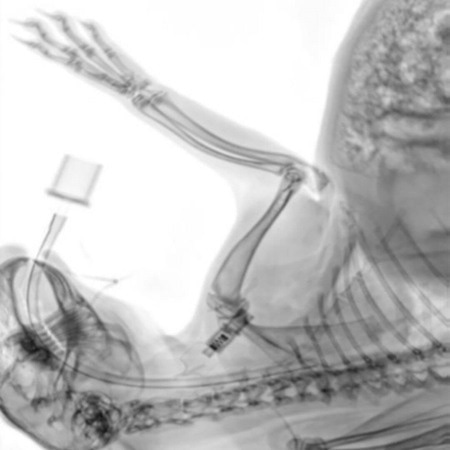

Implants on a sheep bone. The fit of the implants, the progress of healing and fissures on the screw connections are clearly visible. Image Credit: Scintica Instrumentation Inc

Intraoperative control image of a rabbit. The position of the intubation can be determined with great precision. Image Credit: Scintica Instrumentation Inc